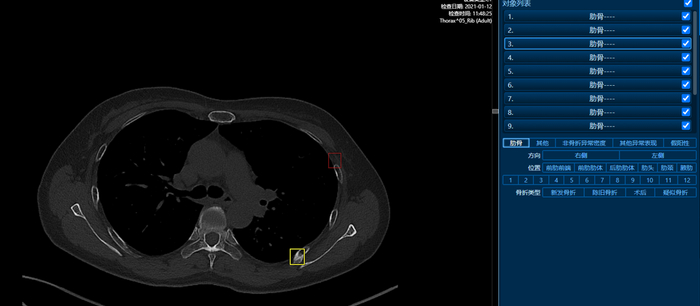

王阿姨做完CT之后,经过华东医院放射科金倞医生的肋骨三位重建+人工智能AI技术分析,终于查出了元凶,发现了王阿姨左侧第7肋骨细微的“弯曲”骨折,找到了这个“会呼吸的痛”的原因,确诊了这类在胸片上不可能发现的骨折(图2)。

图2左侧的图像处理后得到右侧的曲面重组图像用于直观诊断

小知识3:确诊肋骨骨折,一般都需要做肋骨CT三维成像,通过三维重组后可以进行曲面重建,图2中的黄线即专业医师手工沿着肋骨中心截面划线,获得沿肋骨中心截面剖开的图像(图2 右侧图像),这个过程一定是需要专业医师进行操作,即使完成了肋骨三维CT,没有经历这个步骤,也是不能精确诊断的。